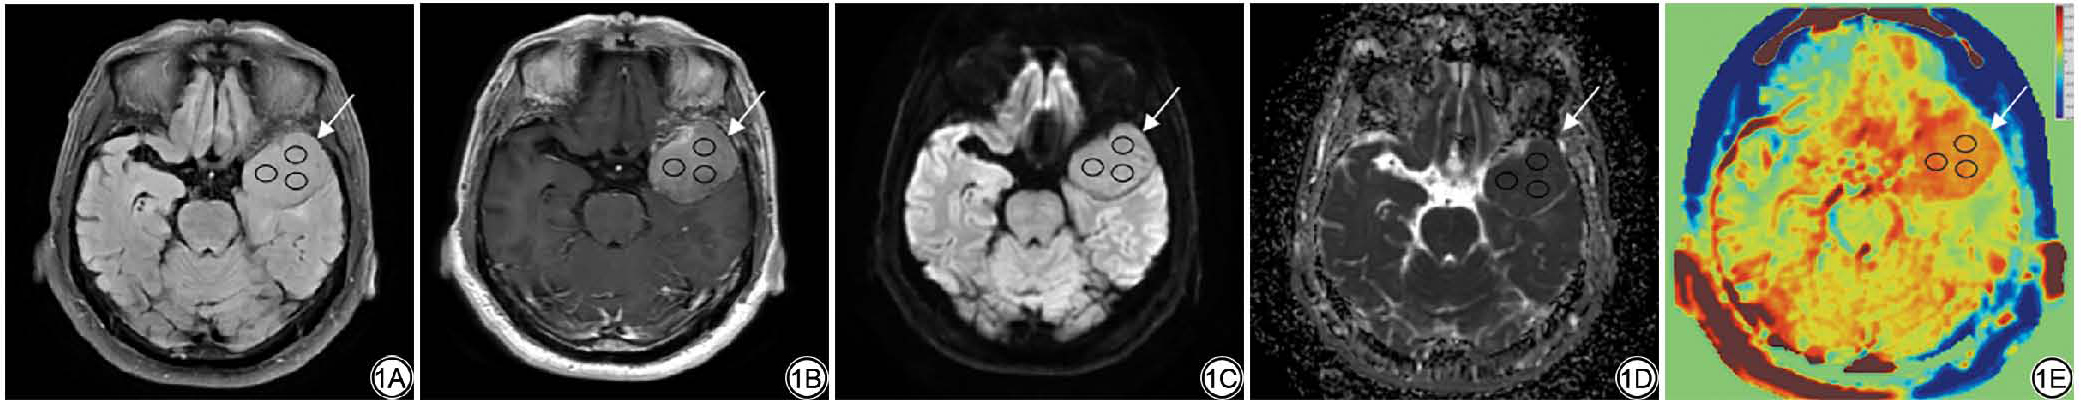

根据本研究设定的纳入及排除标准,71例具有完整病理资料的脑膜瘤患者被纳入,男19例,女52例;年龄为24~79(56.92±10.99)岁。其中,质软组脑膜瘤(图2)33例,非质软组脑膜瘤(图3)38例;两组间在性别、MUSE-DWI信号上差异具有统计学意义(P<0.05),在年龄、肿瘤位置、强化方式、常规MRI信号、有无钙化、水肿、硬膜尾征、WHO分级上差异无统计学意义(均P>0.05)。一般资料见表1

图3  女,68岁,左侧桥小脑角区脑膜瘤(非质软)。3A:术前T2WI;3B:MUSE-DWI衍生成的ADC图呈低信号;3C:MUSE-DWI呈等低信号;3D:APT;3E:免疫组化染色病理切片(×200)。T2WI:T2加权成像;MUSE-DWI:多重灵敏度编码扩散加权成像;ADC:表观扩散系数;APT:酰胺质子转移。

Fig. 3  Female,68 years old, left cerebellopontine angle meningioma (non-soft group). 3A: Preoperative T2WI; 3B: ADC map derived from MUSE-DWI shows low signal intensity; 3C: MUSE-DWI shows iso-to-low signal intensity; 3D: APT; 3E: Immunohistochemical staining of pathological sections (×200). T2WI: T2-weighted imaging; MUSE-DWI: multiplexed sensitivity encoding diffusion weighted imaging; ADC: apparent diffusion coefficient; APT: amide proton transfer.